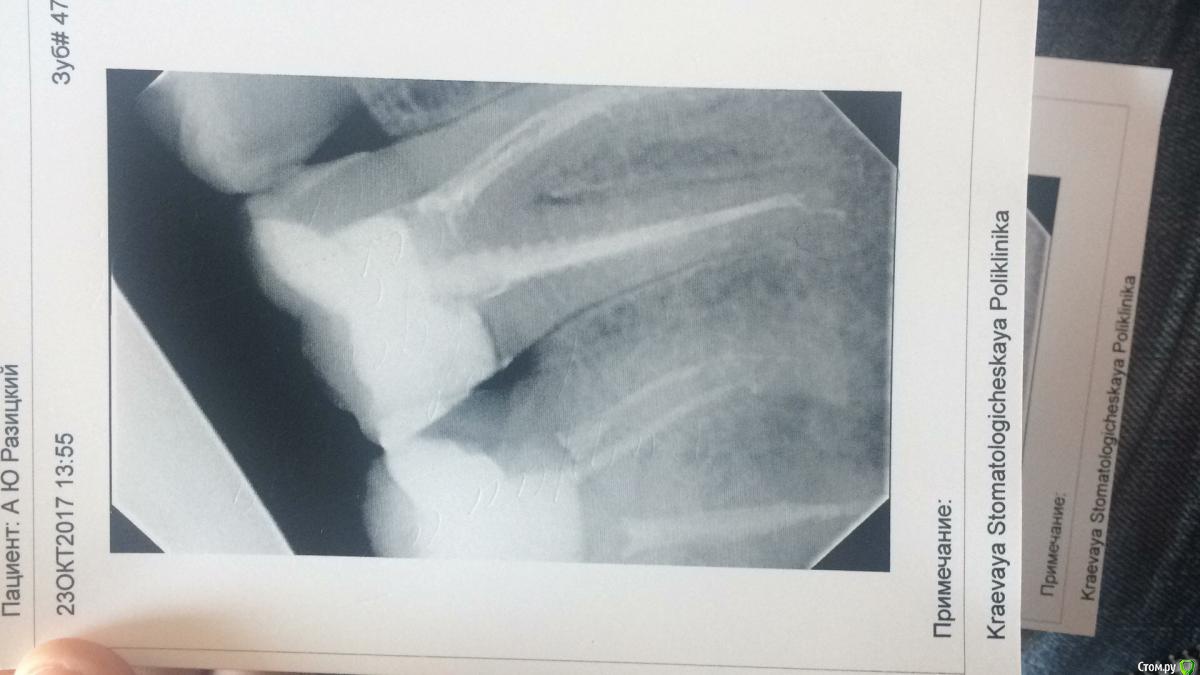

Alexey999 Опубликовано 23 октября, 2017 Поделиться Опубликовано 23 октября, 2017 (изменено) Ни с того ни с сего заболел зуб семерка. Боль при кусании и надавливании. А так же ноющая, ни спать ни вести нормальную деятельность не возможно без кетанова.Обратился к врачу, сделал снимок, сказал все в норме, у мертвых зубов часто так. Сказал воспаление между корнями и пропить антибиотик. Подскажите по снимку, стоит ли обращаться к другому врачу или пить антибиотик? Выкидывать по несколько тысяч просто за консультацию неохото.. Изменено 23 октября, 2017 пользователем Alexey999 Ссылка на комментарий